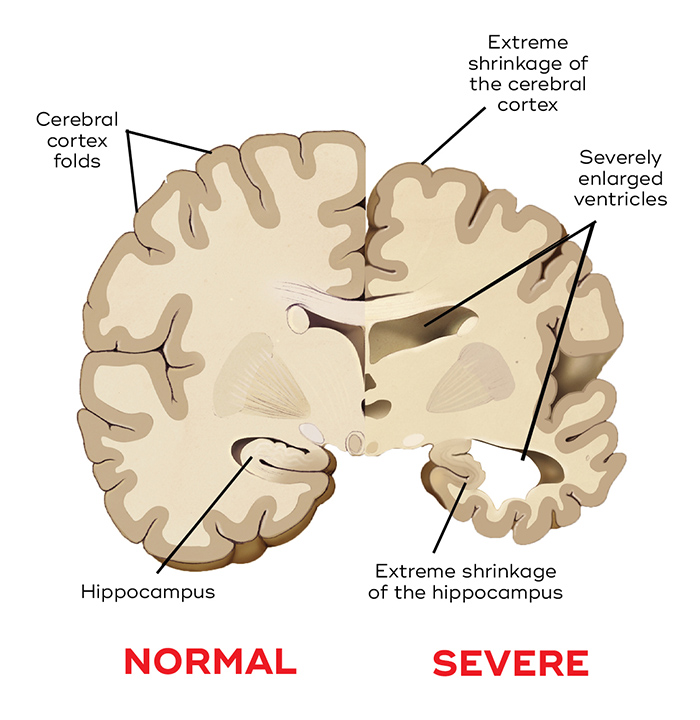

Why Do Ventricles Enlarged In Alzheimer’s – DementiaTalkClub.com

Dementia: Understanding Functional Loss in Your Resident

Alzheimer’s Disease: Stages, Sign and diagnosis Coding – Passionate in …

Anchor2Health: Stages Of #Alzheimer ‘s Disease #Dementia #LongestDay #Brain

Cross-section of the Human Brain with Alzheimer`s Disease Stock Vector …